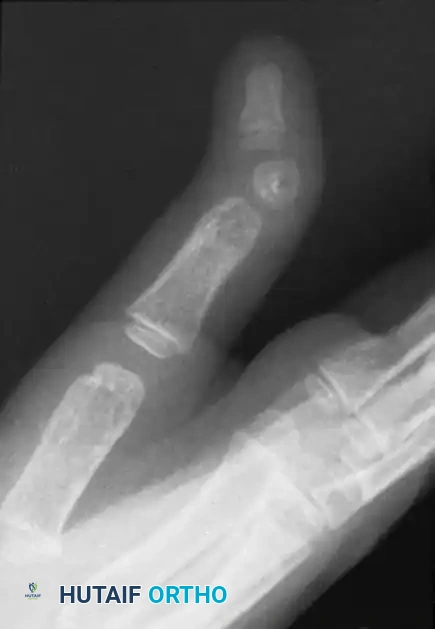

Radiographic appearance of delta phalanx

FIGURE 79-86: Radiographic appearance of delta phalanx. Note the classic triangular shape of the affected phalanx and the continuous bracketed epiphysis tethering the short side of the bone, leading to severe angular deviation.

Radiographs are diagnostic. The affected phalanx appears shortened and wedge-shaped. The continuous epiphyseal bracket is visible along the concave side of the deformity. Early radiographic identification is crucial, as intervention prior to skeletal maturity can alter the growth trajectory.